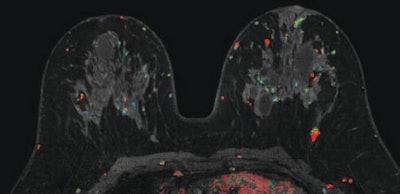

The selection and order of MR images were randomized for each reader to further minimize the potential for bias. Color overlays and CAD tools were available and used at the discretion of the radiologist, while non-CAD interpretations included visual assessment.

Each radiologist was asked to identify any suspicious lesions and to rate the likelihood of malignancy. The readers were also instructed to provide an overall assessment of each case, as a whole, based on the most suspicious lesion identified.